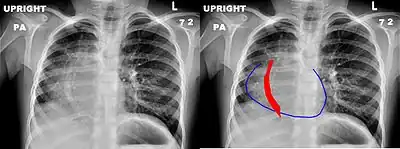

Scimitar syndrome, or congenital pulmonary venolobar syndrome, is a rare congenital heart defect characterized by anomalous venous return from the right lung (to the systemic venous drainage, rather than directly to the left atrium).[1] This anomalous pulmonary venous return can be either partial (PAPVR) or total (TAPVR). The syndrome associated with PAPVR is more commonly known as Scimitar syndrome after the curvilinear pattern created on a chest radiograph by the pulmonary veins that drain to the inferior vena cava.[2] This radiographic density often has the shape of a scimitar, a type of curved sword.[2] The syndrome was first described by Catherine Neill in 1960.[3]

Presentation

The anomalous venous return forms a curved shadow on chest x-ray such that it resembles a scimitar. This is called the Scimitar Sign. Associated abnormalities include right lung hypoplasia with associated dextroposition of the heart, pulmonary artery hypoplasia and pulmonary sequestration. Incidence is around 1 per 100,000 births.[4]